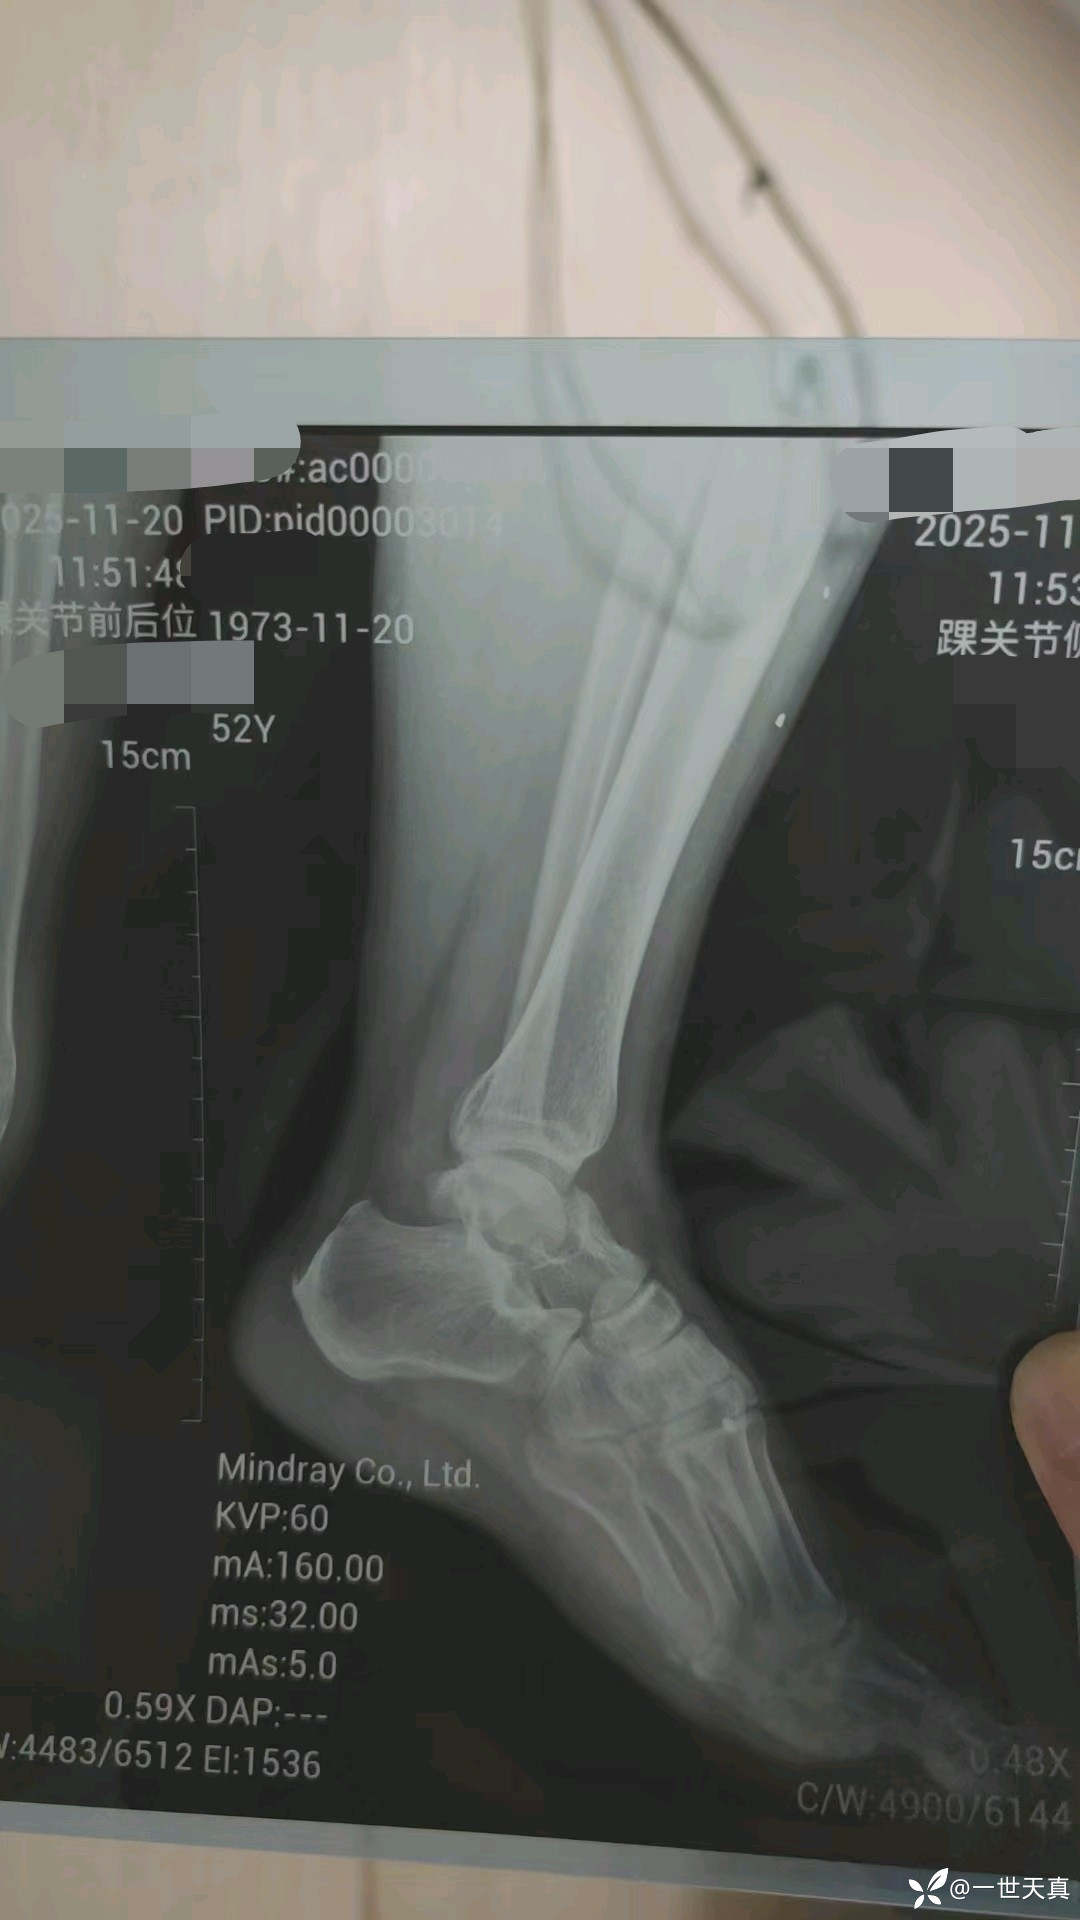

病例踝关节扭伤,少见的骨折,距骨骨折

男性患者,约1小时前下船时踝关节扭伤,自诉落差不高。

距骨骨折,转上级医院进一步诊治。